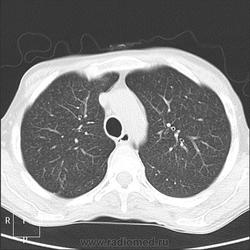

Прозрачность обеих легких равномерно неинтенсивно снижена за счет наличия множественных, плохо дифференцируемых мелкоочаговых теней, сливающихся между собой и расположенных главным образом во внутренних отделах легких, ближе к корням легких, образуя картину «бабочки». Сосудистый рисунок диффузно усилен, в виде радиальных извитых теней за счет перибронхиальной и периваскулярной инфильтрации. Линейные тени пластинчатых ателектазов. Корни легких малоструктурны. Органы средостения не смещены. Сердечная тень не увеличена."

Я не вижу "Бабочку", а Вы?

Из-за почечной недостаточности контрастирования не будет. Такая картина в легких мне впервые попадается. Есть несколько вариантов, но очень хочется услышать мнения коллег! Какие будут мысли?

В легких - рентгенограмму я описала как усиление за счет интерстициального компонента. Корень кажется обрубленным: из-за асцита высоко стоит диафрагма, нижние отделы легких поджаты. Пневмосклероза я не вижу. А по КТ не знаю, как интерпретировать: интерстициальный отек, токсический васкулит?

Тогда, учитывая всё вышесказанное, вероятно интерстициальный отёк ( гипопротеинемия, почечная недостаточность, токсическое поражение...)

Интерстициальный отек легких. Хронический калькулезный панкреатит. Киста хвоста поджелудочной железы, без биопсии уверенно раковое перерождение не исключить. Киста сальниковой сумки /вероятно тоже панкреатического генеза/. Жировой гепатоз печени с портальным циррозом /биопсия/. Камень устья? пузырного протока. Геморрагические кисты почек??? Асцит.

Парочка моих шаблонов, наверное первый соответствует настоящему состояниюПрозрачность обеих легких равномерно неинтенсивно снижена за счет наличия множественных, плохо дифференцируемых мелкоочаговых теней, сливающихся между собой и расположенных главным образом во внутренних отделах легких, ближе к корням легких, образуя картину «бабочки». Сосудистый рисунок диффузно усилен, в виде радиальных извитых теней за счет перибронхиальной и периваскулярной инфильтрации. Линейные тени пластинчатых ателектазов. Корни легких малоструктурны. Органы средостения не смещены. Сердечная тень не увеличена.

Прозрачность обеих легких неравномерно, преимущественно в нижних отделах, неинтенсивно снижена за счет наличия множественных, плохо дифференцируемых крупноочаговых теней, сливающихся между собой и расположенных главным образом во внутренних отделах легких, ближе к корням легких, образуя картину «бабочки». В прикорневых и паравертебральных отделах значительное усиление сосудистого рисунка, размытого грубопетлистого, обусловлено венозным полнокровием. Тени венозных сосудов определяются, как поперечно расположенные полосы с нерезкими контурами, преимущественно в нижних отделах. Определяются горизонтальные линии Керли вследствие интерстициального отека междольковых перегородок Корни легких расширены малоструктурны. Органы средостения не смещены. Сердечная тень увеличена в поперечнике, талия сглажена, аорта уплотнена, умеренно развернута

Я не вижу "Бабочку", а Вы?